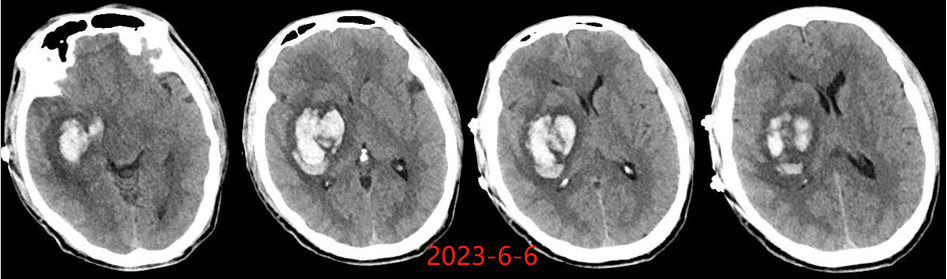

入院后于当地医院完善头颈部CTA检查未见明显血管发育异常,于2023-6-7行血肿钻孔引流术+脑室内颅内压监护探极置入术,引流一周后拔除引流管,期间未行尿激酶注射,患者反应情况逐渐好转,肌力未见明显改善。于出血后3周左右脑水肿基本消退后出院行康复治疗,治疗过程中患者肌力曾有所改善,左侧肢体肌力最好可达3级。术后3月左右患者一般状态逐渐变差,无发热,神志逐渐进展为昏睡状态,左侧肢体肌力1级,复查颅脑CT示水肿较前明显加重,颅脑MRI示右侧基底节区长T1长T2团块状病变,内有囊变,呈不均匀菜花样强化,考虑为高级别胶质瘤可能性大。遂行开颅病灶大部切除+去骨瓣减压术,术后病理提示高级别胶质瘤伴囊变,后续行同步放化疗STUPP方案,PTV:60Gy/30F/6周,替莫唑胺350mg化疗。患者右侧基底节区病灶相对稳定,2024-9-3复查颅脑MRI可见脑室内新发病灶。患者目前KPS 60分,神志清醒,精神差,反应迟钝,语言对答部分切题,右侧肢体自主活动,左侧肢体肌力2级。

胶质瘤出血灶周围水肿一般较广泛,同血肿期龄存在明显不符的征象,出血后早期即有明显水肿,此时并非血肿引起,而是肿瘤机械压迫、脑皮质受损,肿瘤细胞的分泌作用及细胞毒性等多因素共同作用所致,且水肿持续时间长。 高血压性脑出血的水肿一般在出血后 3 h 出现,48 h 达高峰,4 d 后开始逐渐消退,2-3 周后基本消失。该患者脑水肿出现的时间相对较早、重,且持续时间长,有别于一般的高血压脑出血。若该患者若第一次出血行钻孔引流时,术中能留取标本查到肿瘤脱落细胞,则会使该患者的诊断提前;当然对于该患者也不能完全排除单纯脑出血后,周围脑组织水肿缺氧等微环境的改变诱发胶质瘤的发生。总之,对于既往无脑出血高危因素且脑血管检查未见明显异常的脑出血患者,若脑水肿出现早且持续时间长,应警惕肿瘤卒中可能。